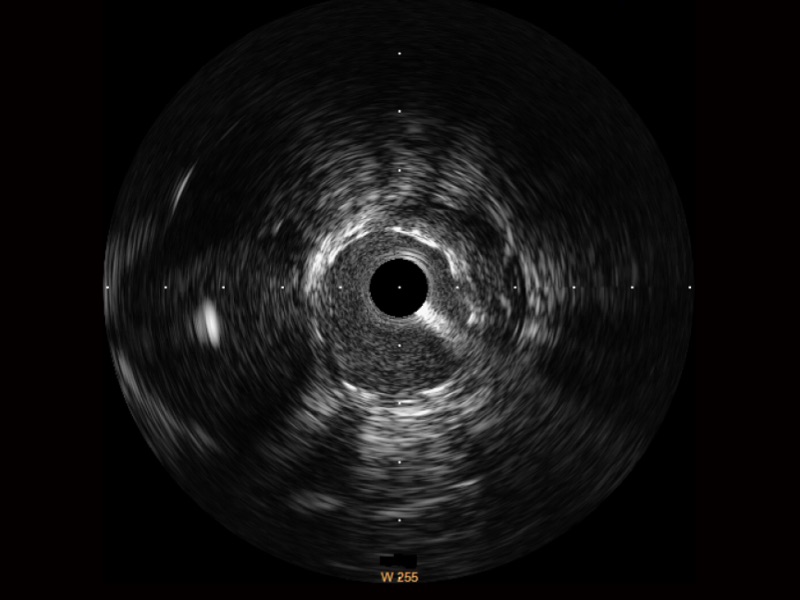

百老汇电子游戏官网宽频IVUS图像

对比传统IVUS导管成像,百老汇电子游戏官网宽频IVUS图像的近场支架梁显影更细腻,远场中膜外血管仍清晰可辨,兼顾远中近,兼顾分辨力与穿透深度